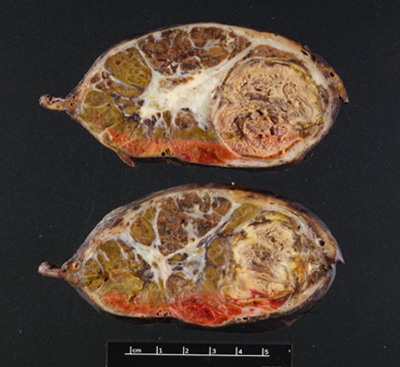

Figure 2. (Gross Photo, Cross Section) Cross sections show multilobulated tumor with areas of necrosis and central scarring.